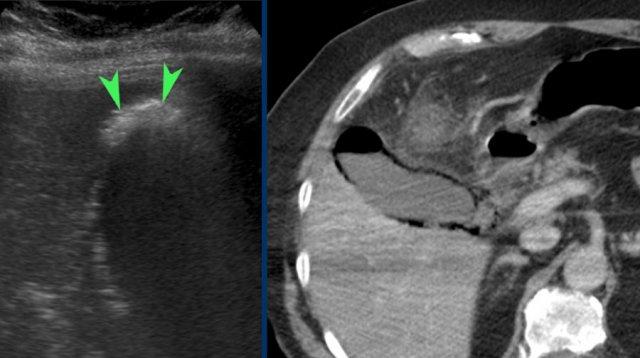

Hình ảnh của một bệnh nhân được nghi ngờ lâm sàng là thủng dạ dày.

CT cho thấy một số sỏi trong túi mật có hình dạng tròn.

Siêu âm bổ sung xác nhận rõ ràng tình trạng phình to túi mật (đầu mũi tên).